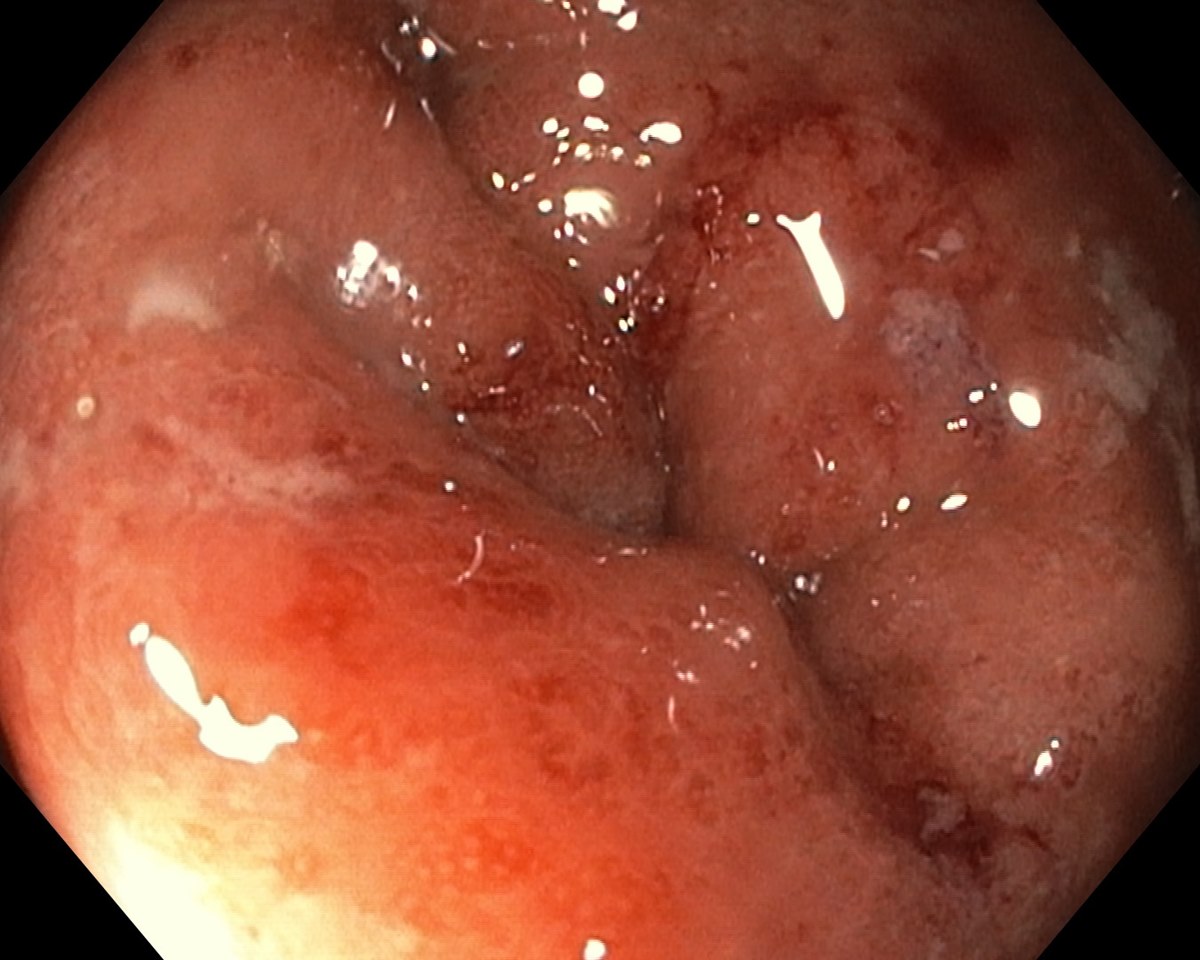

A Distal Ulcerative Colitis, Proctosigmoiditis Ulcerosa

A Distal Ulcerative Colitis.

A Distal Ulcerative Colitis